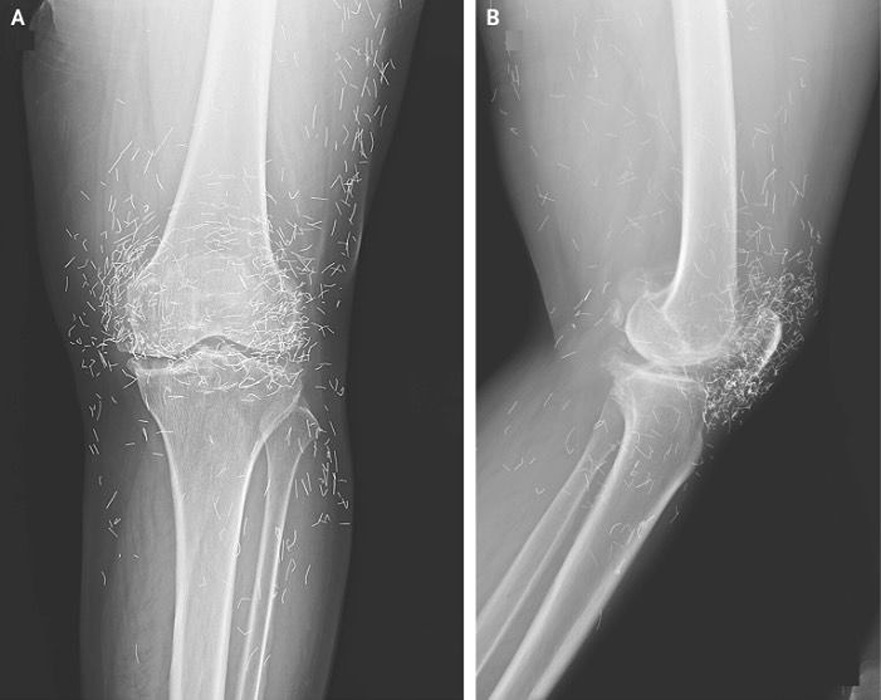

And here’s a big one: if you ever need an MRI, it could be dangerous. The strong magnets might shift the needles, potentially harming blood vessels or other tissues. 0 “An X-ray showing hundreds of tiny gold threads embedded around the knee joint from acupuncture treatment.” “LARGE” 2 ”” “LARGE”

Frustrated, she decided to try acupuncture instead. This ancient practice uses thin needles inserted at specific points to ease pain and treat various issues. In her case, the treatment involved gold threads or tiny needles that were deliberately left in place around her knees for ongoing relief—a method sometimes used in parts of Asia for arthritis.

Plus, those metal bits can mess with medical scans. They might hide important details on X-rays, making it harder to see what’s really going on.